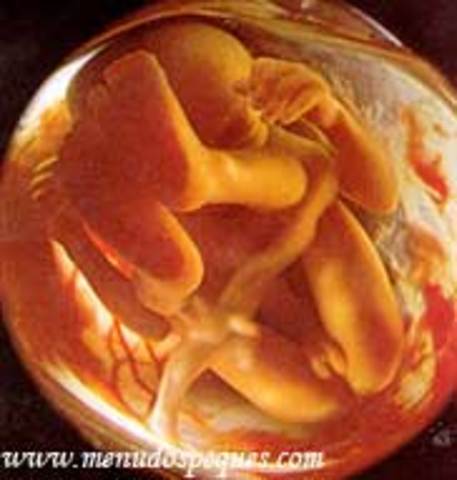

• semana 12

semana 12

En la etapa fetal el crecimiento es notable. En la novena semana el feto pesa 8 gramos y al momento de nacer alcanza un peso de 3000g aprox. La cabeza sigue muy grande aunque el tronco sigue creciendo poco a poco de tamaño, la región pélvica se mantiene estrecha.

• semana 14 de embarazo

semana 14 de embarazo

En esta semana se aprecia su aspecto humano, las orejas en su posición definitiva y los párpados de mantienen cerrados aun.